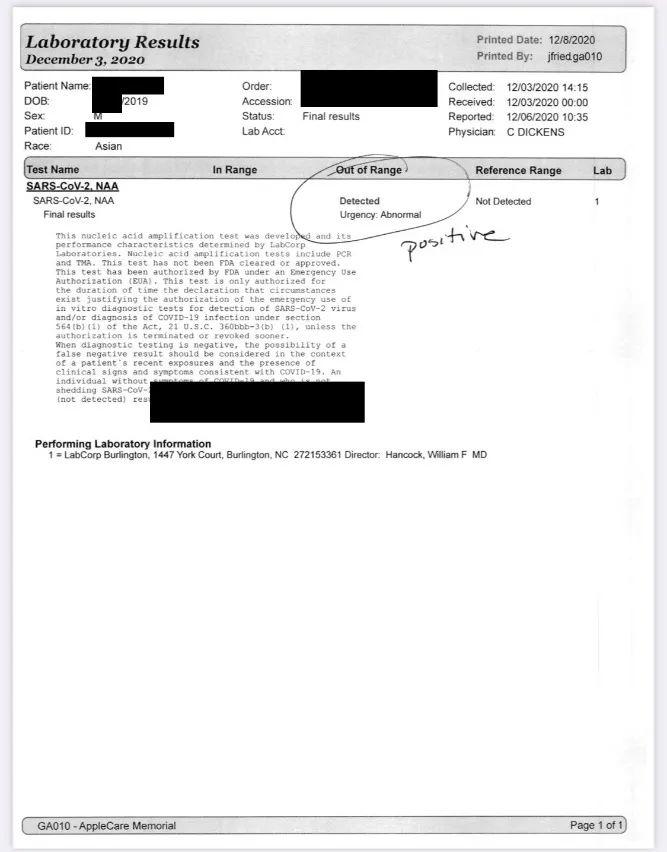

由于10岁以下不能在CVS 做DRIVE THRU测试,所以我们去了Applecare 做PCH 测试。(这里提醒大家记得要提前预约,不然就会像我们一样等了一个半小时才能测。)帮我们检查的护士说,最近确实多了很多人来做检测,但大部分人都是Negative的,就算positive很多都是轻症,有的更是无症状,只有一小部分是严重的。

当值的医生听我说了症状后,已经可以肯定我确诊了;而儿子,从他眼周的红疹判断,应该是得了流感或新冠,因为这些红疹多数是因病毒而起的,并不是那种川崎症,这让我放下了心头大石;我老公完全没任何症状,医生推断他可能是无症状感染者。

医生给我开了4天的处方药,分别是消炎药和抗生素,而宝宝目前没有专门治疗新冠的药可吃,所以如果发烧的话,还是吃泰诺或感冒药。 我们每天都有吃维他命,包括维B、维C、维D3,我还做了鸡汤每天喝,而且一直有吃感冒药。Boss就继续喝苹果洋葱水,以及吃Gummy Bear补充维他命。

检测3天后,我们收到了结果:我跟儿子都是Positive,爸爸是Negative,估计他可能本身有抗体。